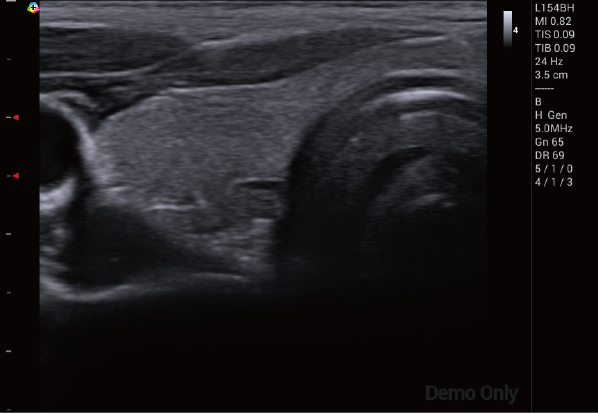

臨 床 圖 集